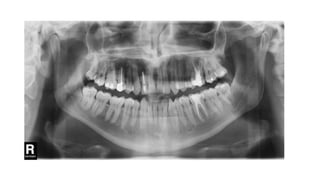

Interpretation of panaromicimage • Under negatoscope or in compute 1.Dentition 2.Mid facial region or upper jaw 3.Lower jaw 4.Soft tissues 5.Check peripheries

Dentition • Count theteeth; note the missing • Supernumerary and impacted teeth • Caries and abscess • Fractures • Lucent or sclerotic lesions

Mid facial region/upperjaw • Facial bones, sinuses and soft tissue • Facial bones; temporal, zygomatic, mandibles, maxilla, frontal, ethmoid and maxillary sinuses, nasal septum, concha • Look for fracture • Cystic or sclerotic lesion • Maxillary sinuses • Nasal cavity

Lower jaw • Mandibularcondyles and TMJ • Coronoid process • Ramus and body of mandible • Alveolar processes

Periphery/soft tissues • Hyoidbone • Spine • Pharynx • Zygomatic arch